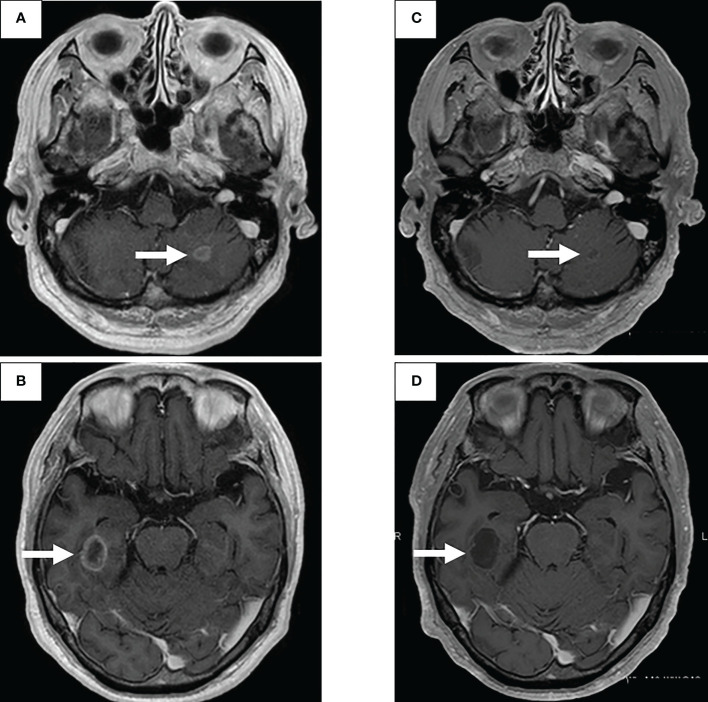

图1:在第一次就诊到开始进行第二次治疗期间,患者7年间原发病灶的顺序图像

通过支气管镜对原发病灶进行再活检,细胞学评估显示V级腺癌,组织学评估证实了这一结果。肿瘤正确用药850基因检测确认患者为RET融合基因阳性,随后于第二天给予240mg塞尔帕替尼。第13天的CT显示与基线影像相比(图1H),所有转移病灶,包括脑转移(图2C、D),均有良好的全身反应。由于2级肝酶升高,继续给予剂量减少的塞尔帕替尼(每天160mg)。使用高敏感度的下一代测序(NGS)面板系统:肺癌紧凑面板,并使用细胞学刷液进行RNA检测,证实了融合基因KIF5B外显子15;RET外显子12(K15RET12)。肿瘤正确药基因解码基因检测还能够从7年前的胸腔积液细胞块的福尔马林固定石蜡包埋(FFPE)标本中进一步确认RET(图3A、B),这些标本在恶性细胞的形态学上与再活检样本相似,具有大核仁(图3C、D)。从初始细胞块样本中收集到的RNA(1256ng)具有RNA整合数(RIN)值为4.8。单重PCR和NGS检测均检测到了K15RET12融合峰(图3)。